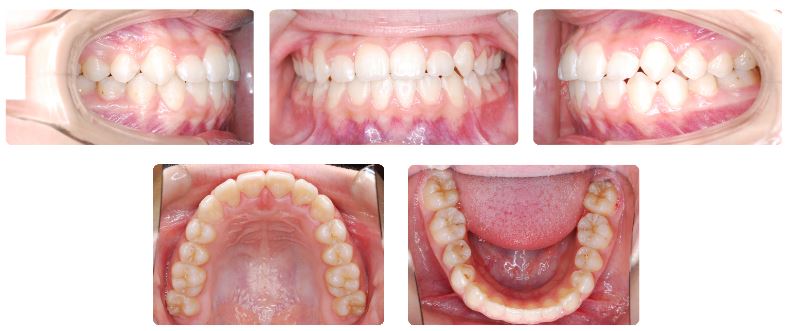

装置名:可撤式装置 → マルチブラケット装置

治療期間:3年9ヶ月

永久歯列への交換末期で、最初の半年ほど取り外し式の拡大装置を上あごに夜間のみ装着して上あご歯列幅の拡大を行いました。

ワイヤーの固定装置による動的処置を行いながら上下あごの12歳臼歯(第二大臼歯)が正常な位置に萌出するように誘導しました。